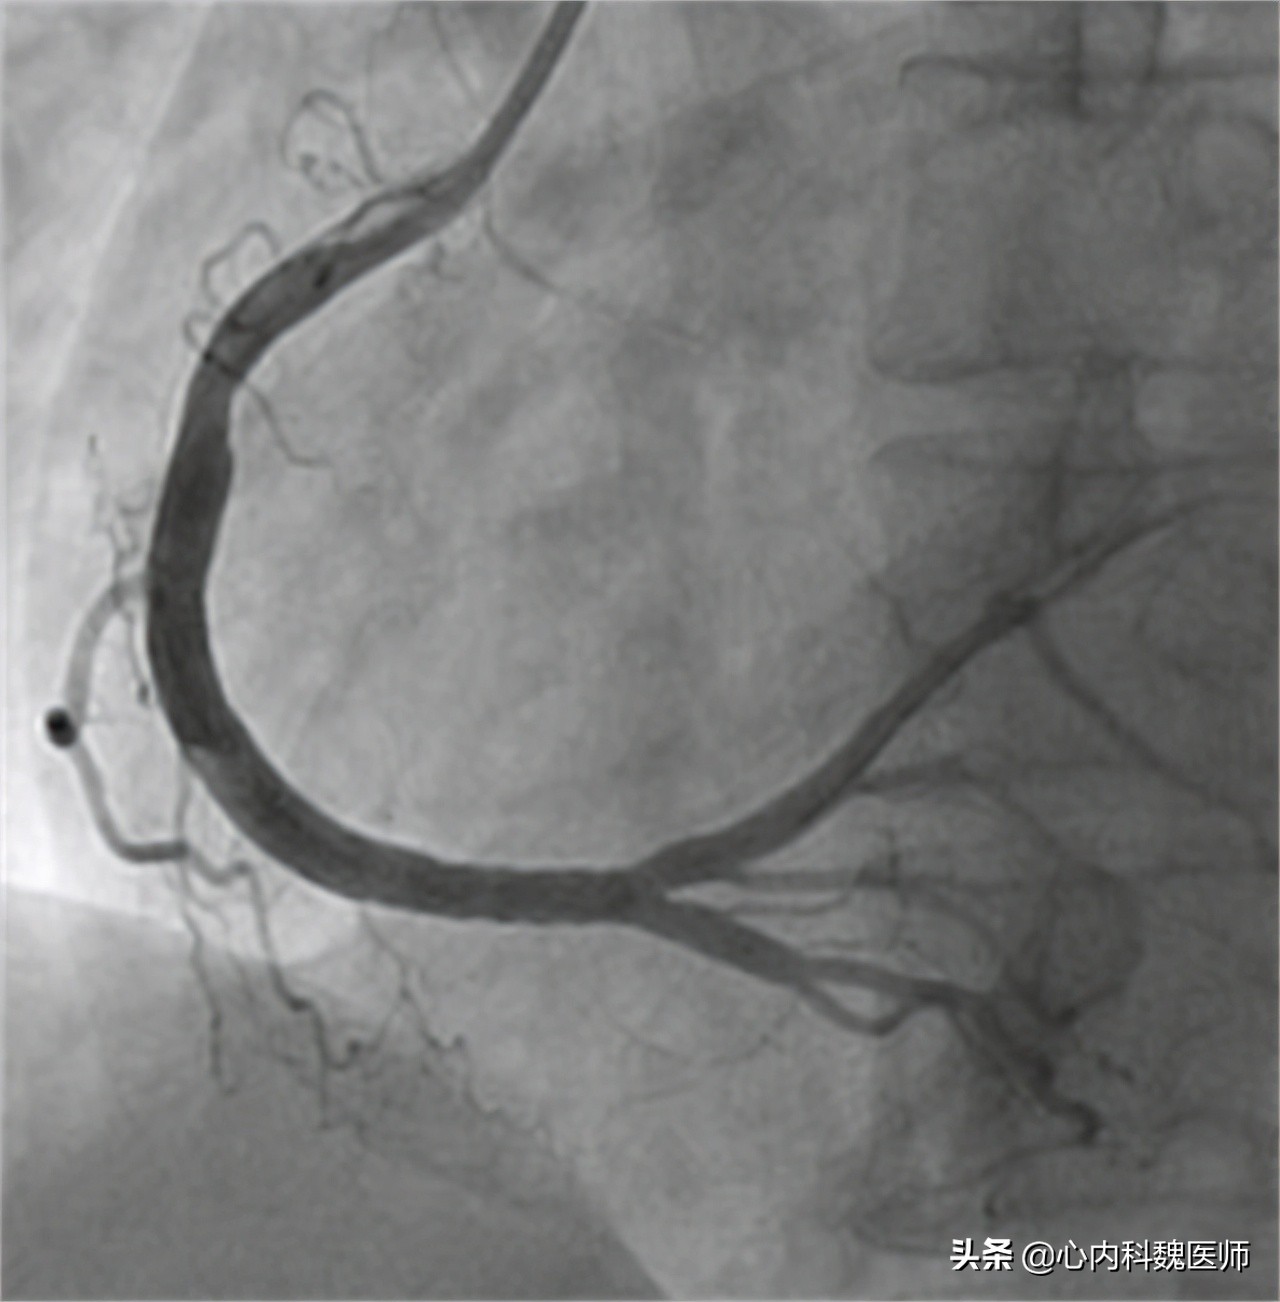

高大爷向医生说明了自己8年的冠心病史和一直没有服用药物的状态,医生害怕高大爷的病情进一步加重,于是做了简单的查体后就安排了高大爷住院进行心脏冠脉造影的检查。检查结果出来后,医生十分奇怪高大爷的情况。

患者体温36.5℃、血压130/90、身高168cm、体重68kg。心电图提示心脏存在明显早搏现象。心脏造影显示主动脉堵塞百分之二十三,排除冠心病。

医生:“冠心病的最佳诊断方法就是做 冠状动脉造影 ,因为这是最直观观察冠状动脉情况的检查。但是鉴于这种检查对患者会造成一定的创伤,所以我们只有在高度怀疑患者有冠心病的时候才会考虑。”

医生:“还有一种检查被叫做 冠脉CT ,这种检查虽然没有造影那么直观,但是可以作为辅助诊断冠心病的检查,当检查结果提示患者的冠状动脉重度狭窄时,大概率就是冠心病的症状,如果需要进一步确诊可以再考虑冠状动脉造影,检查具体堵塞的位置。”